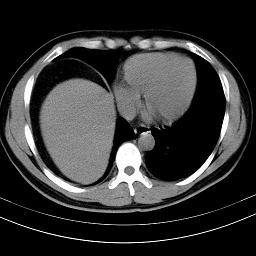

标题: CT18388:肝脏膈肌间隙内大量脂肪密度影 [打印本页]

标题: CT18388:肝脏膈肌间隙内大量脂肪密度影

是脂肪不是气体,有时候会碰到这样的病人,脂肪过多吧。

膈下脂肪沉积。

考虑膈下脂肪沉积。

激素治疗的病人容易脂肪沉积